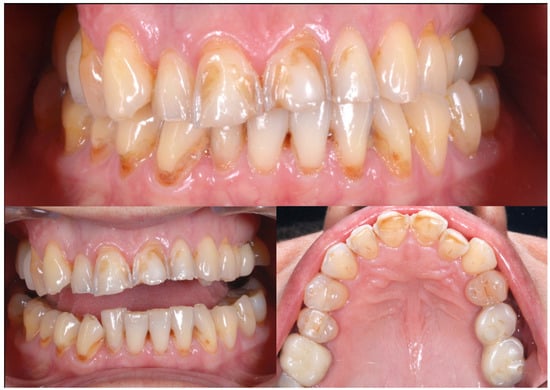

2.2. Clinical Example

| Before | After | |

|---|---|---|

| Disharmonious smile | Yes | No |

| Dyschromia, dysmorphia, abrasions, and erosions of teeth | Yes | No |

| Anterior crowding in the upper arch | Yes | No |

| Anterior crowding in the lower arch | Yes | No |

| Upper transverse discrepancy | Yes | No |

| Presence of buccal corridors or black tunnels | Yes | No |

| Curve of Spee alteration | Yes | No |

| Curve of Wilson alteration | Yes | No |

| Functional movements with altered guides | Yes | No |

| Pain and/or noise ATM | Yes | No |